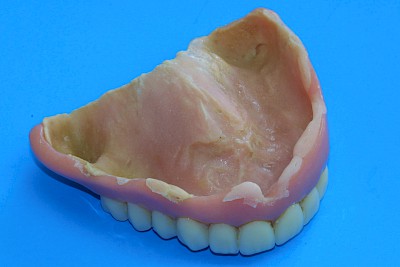

Weichbleibende Unterfütterung

Weichbleibende Unterfütterungen werden durchgeführt, wenn es immer wieder zu Prothesendruckstellen kommt. Allerdings lassen sich weichbleibende Unterfütterungsmaterialien nicht so gut reinigen. Es kommt schneller zu Belagsbildungen und Pilzbefall. Mit der Zeit können zudem die Materialien verspröden, was die Belagsbildung weiter begünstigt. Dann spätestens ist es sinnvoll und notwendig, den Zahnarzt zu verständigen.

Weiche Beläge lassen sich in den meisten Fällen mit Zahnprothesenbürsten und Zahnpasta entfernen. Auch Reinigungstabletten können hilfreich sein. Haftcreme lässt sich mit Kompressen oder Pflaumentupfern leichter entfernen – sowohl von den Schleimhäuten der Kiefer wie auch von den Prothesen.

Mindestens einmal im Jahr ist eine professionelle Reinigung der Prothesen durch den Zahnarzt zum Beispiel in einem sogenannten Ultraschallbad sinnvoll. Marktübliche Geräte für den Heimgebrauch sind oft nicht stark genug. Auch bei allen anderen Auffälligkeiten sollte ein Zahnarzt gerufen werden, um mögliche Behandlungen einzuleiten.

Belag

Weiche Beläge oder Speisereste sollten zunächst durch Intensivierung der Prothesenpflege beseitigt werden. Harte Beläge, die sich auch mit Zahnprothesenbürsten entfernen lassen, können durch einen Zaharzt mit speziellen Prothesenreinigungsgeräten (Ultraschallbad) entfernt werden.